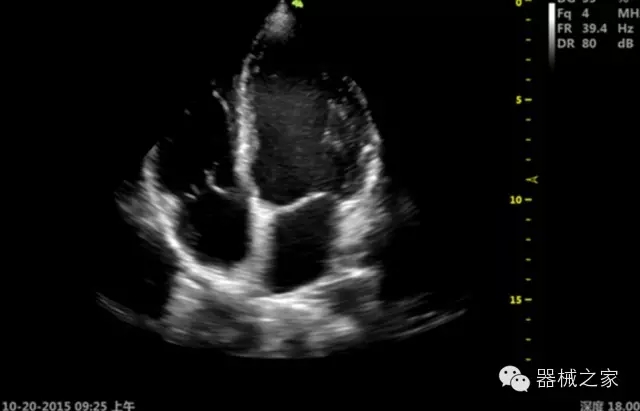

臨床圖片賞析

產(chǎn)品特點(diǎn)

·獨(dú)有的RF平臺提高微小細(xì)節(jié)顯示、圖像對比度和邊界清晰度;

·特有的XCEN探頭,超寬的帶寬,表現(xiàn)更高分辨率和對比度;

·單晶純凈波探頭提供更佳的穿透力和彩色敏感度;

·完整的3D/4D臨床應(yīng)用,STIC, MCUT 和Auto NT等滿足產(chǎn)科所有應(yīng)用;

·更高的HQ羊膜腔鏡成像技術(shù)精細(xì)觀察每一個暗區(qū)細(xì)節(jié);

·智能的觸摸屏界面,能任意角度方位旋轉(zhuǎn)3D圖像,以及注釋快速標(biāo)記,提供直觀與便捷的操作,提高了工作效率;

介入室/手術(shù)室

·Needle Enhancement 穿刺增強(qiáng)技術(shù),清晰顯示穿刺針尖,定位目標(biāo)精確穿刺;

·智能的聲控功能,以及全屏顯示真正意義上解決醫(yī)生術(shù)中應(yīng)用;

Xcen探頭技術(shù)

·獨(dú)有的Xcen高頻18MHz探頭,使微小病灶的顯示成為現(xiàn)實(shí),為臨床提供了更廣泛的臨床應(yīng)用;

·Xcen超寬頻帶探頭技術(shù)比常規(guī)探頭頻寬提高了30%,具有更廣泛的臨床應(yīng)用,更高的頻率讓我們獲得了更好的細(xì)微分辨率和對比度的圖像;

肌骨理療

·智能感知組織特異性的VTissue技術(shù),結(jié)合特有高達(dá)22MHzXcen線陣探頭, 以及獨(dú)有敏感的RF射頻血流提供了優(yōu)異臨床圖像;

·智能的教學(xué)操作流程提供全面及專業(yè)的操作步驟指導(dǎo),便捷藍(lán)牙傳輸保障信息流暢;

便捷傳輸功能

·藍(lán)牙傳輸/ WIFI 郵件/ 移動網(wǎng)絡(luò)/ DICOM;

·ICU/CCU;

·飛依諾特有心臟純凈波探頭提供更好的穿透力和彩色敏感度,以及結(jié)合TView梯形拓展改善困難病人深部組織成像;

·獨(dú)有RF敏感血流使得心臟血流完美呈現(xiàn);